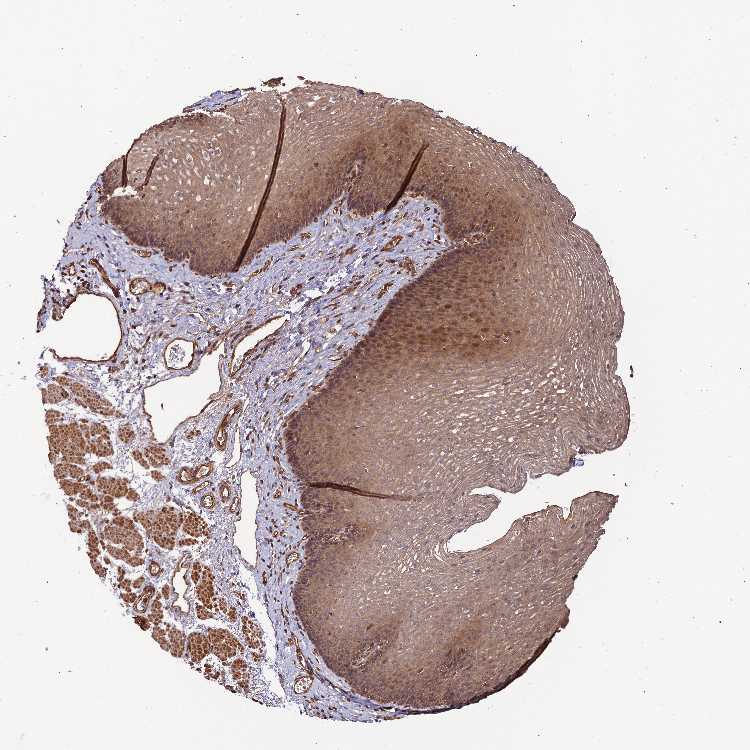

ESOPHAGUS - Antibody stainingi

Antibody staining in the annotated cell types in the current human tissue is reported as not detected, low, medium, or high, based on conventional immunohistochemistry profiling in selected tissues. This score is based on the combination of the staining intensity and fraction of stained cells.

Each image is clickable and will lead to virtual microscopy that enables deeper exploration of all samples and also displays staining intensity scores, fraction scores and subcellular localization as well as patient and tissue information for each sample.

Antibody HPA042907

Squamous epithelial cells Medium